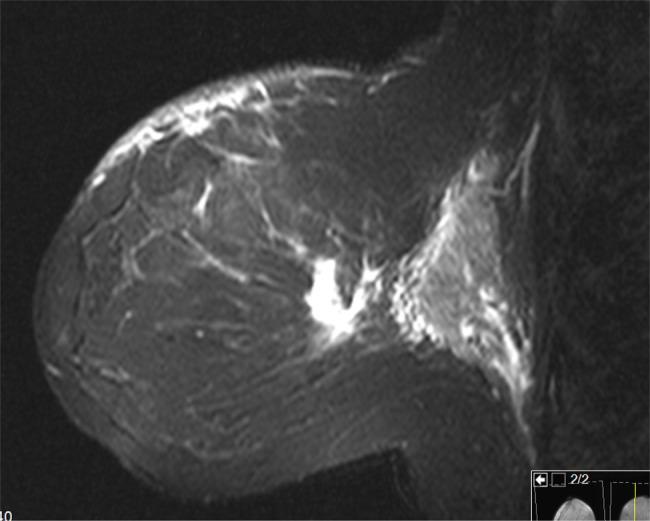

Breast cancer is the most common cancer in women in the USA, with the lifetime incidence of 1 in 8 women. Dermatomyositis (DM) is an uncommon idiopathic inflammatory myopathy that can manifest as a paraneoplastic syndrome of an underlying malignancy. Here, we report a case of a patient who presented with breast cancer and DM symptoms. The patient's rash and muscle weakness progressed during the workup of her breast cancer, while she was already started on medical treatment of these symptoms with oral prednisone. Her cutaneous and musculoskeletal improved dramatically following the treatment of her breast cancer. Our case report describes the rapid progression and regression of her symptoms emphasizing the benefit of early diagnosis and treatment of DM as well as the underlying breast cancer.

乳腺癌是美国女性中最常见的癌症,八分之一的女性一生中会患乳腺癌。皮肌炎(DM)是一种罕见的特发性炎性肌病,可表现为潜在恶性肿瘤的副肿瘤综合征。在此,我们报告一例出现乳腺癌和皮肌炎症状的患者。该患者在乳腺癌检查期间皮疹和肌肉无力症状加重,而此时她已开始口服泼尼松对这些症状进行药物治疗。在乳腺癌治疗后,她的皮肤和肌肉骨骼症状显著改善。我们的病例报告描述了她症状的快速进展和消退,强调了早期诊断和治疗皮肌炎以及潜在乳腺癌的益处。